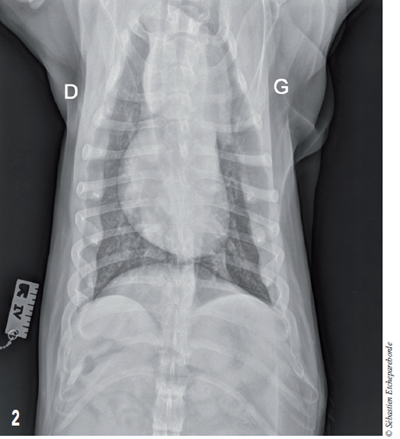

Photo 2 - Vue ventrodorsale du thorax

On distingue que la masse s’étend sur la gauche du coeur.